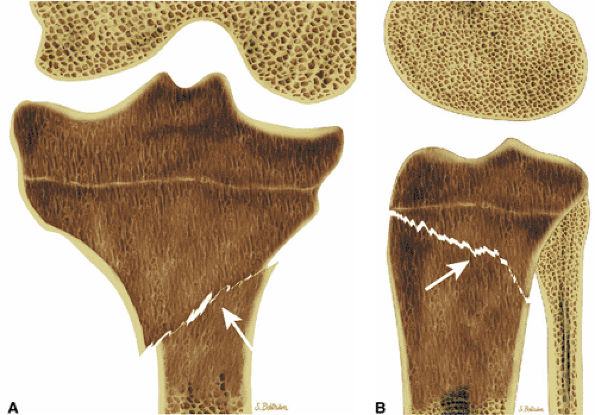

FIGURE 13.27 ● Hodgkin disease of the proximal tibia. Focal marrow infiltration from lymphoma is demonstrated on coronal (A) and sagittal (B) graphic illustrations. A pathologic fracture is present (arrows).

|